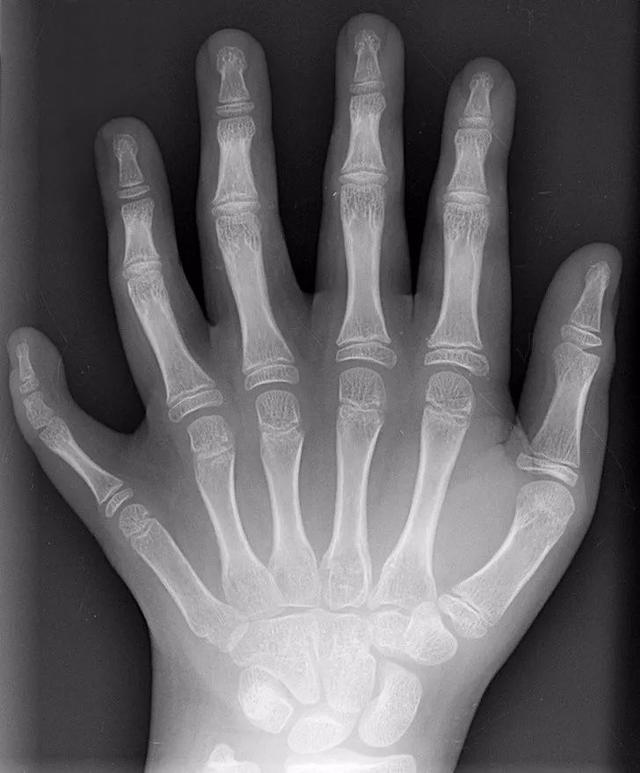

六根手指的X光图